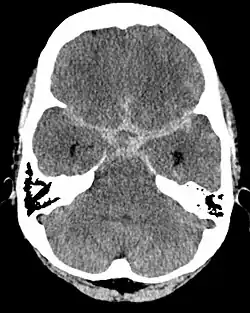

Subarachnoidalblutung

Die Subarachnoidalblutung (SAB) liegt unter der Spinnengewebshaut (Arachnoidea), die das Gehirn einkleidet. Diese Art von Blutung ist arterieller Natur und hat als führendes Leitsymptom ein plötzliches Kopfschmerzereignis (Vernichtungskopfschmerz) mit Übelkeit und Erbrechen.

Zu einer Subarachnoidalblutung kann es bei einer Ruptur eines Aneurysmas (arterielle Gefäßwandfehlbildung, die zu einer Gefäßaussackung mit mangelhafter Muskelschicht führt) der Arterien vom Circulus arteriosus cerebri (Willisi) oder den daraus hervorgehenden großen Arterien kommen. Bei einer Subarachnoidalblutung ist im Gegensatz zu den beiden anderen Blutungsarten Blut im Liquor cerebrospinalis nachweisbar.

Je nach Ursache der Blutung wird die Subarachnoidalblutung unterschiedlich behandelt, von operativ bis endovaskulär.